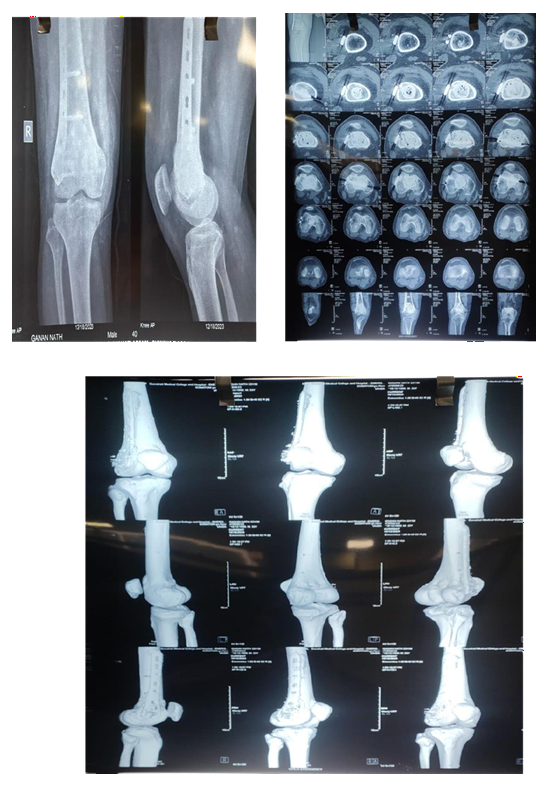

Case 2:

MRI

Pre Denosumab

Post Denosumab

Intraoperative

Post Operative